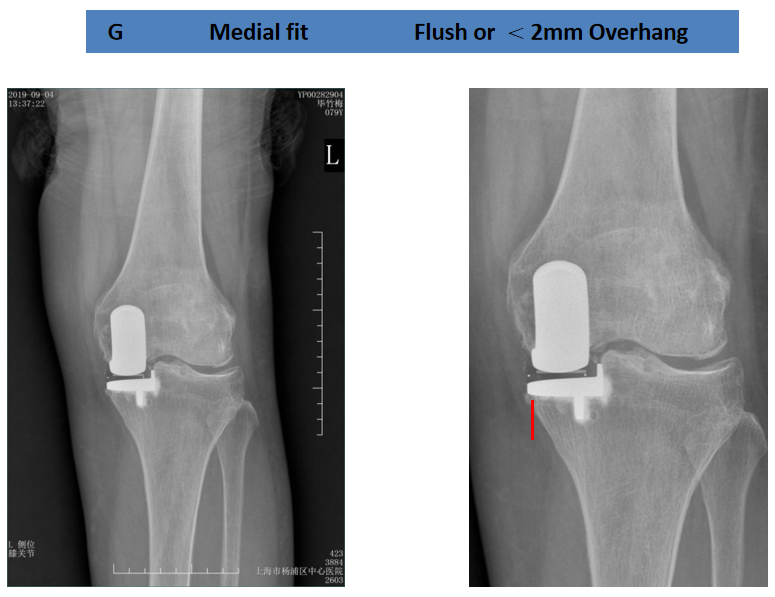

病例1

术后X-ray:正位片内旋,显示胫骨假体大小及位置佳(垂直截骨在棘突顶点、与内侧缘齐平、无内外翻)。

病例2

术后X-ray:标准正位片,显示胫骨假体大小及位置佳(垂直截骨在棘突顶点、与内侧缘齐平、无内外翻)。